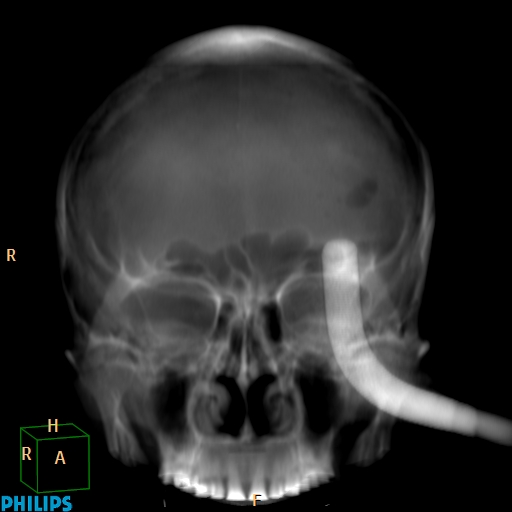

Accident de travail, chute sur une barre de fer. La barre de fer a été coupé sur le chantier pour dégager le patient A noter, comme on peut le voir sur la dernière image, que le patient était conscient et réveillé